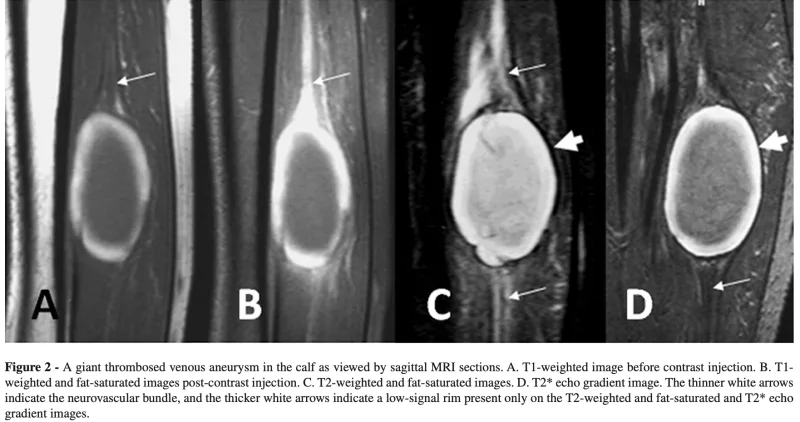

T1強調画像 (A)で, 腫瘤内部の表面近くが白く写り, 中央が黒く写るのが特徴的な所見です.

特徴的な写り方からは, 静脈性血管瘤(venous aneurysm)が疑われました.

静脈性血管瘤は, 孤立性の静脈拡張と定義される稀な疾患です.

下肢の深部静脈に生じた瘤は, 肺動脈血栓塞栓症の原因となるため, 積極的に手術療法が行われ, 瘤縫縮ないし瘤切除+血行再建が推奨されています.

一方, 表在静脈に生じた瘤は, 重篤な合併症を併発することは稀であるため, 美容的な理由, 痛み, 腫脹などの症状がある場合に手術が行われ, その多くは切り取るだけ(単純切除)です.